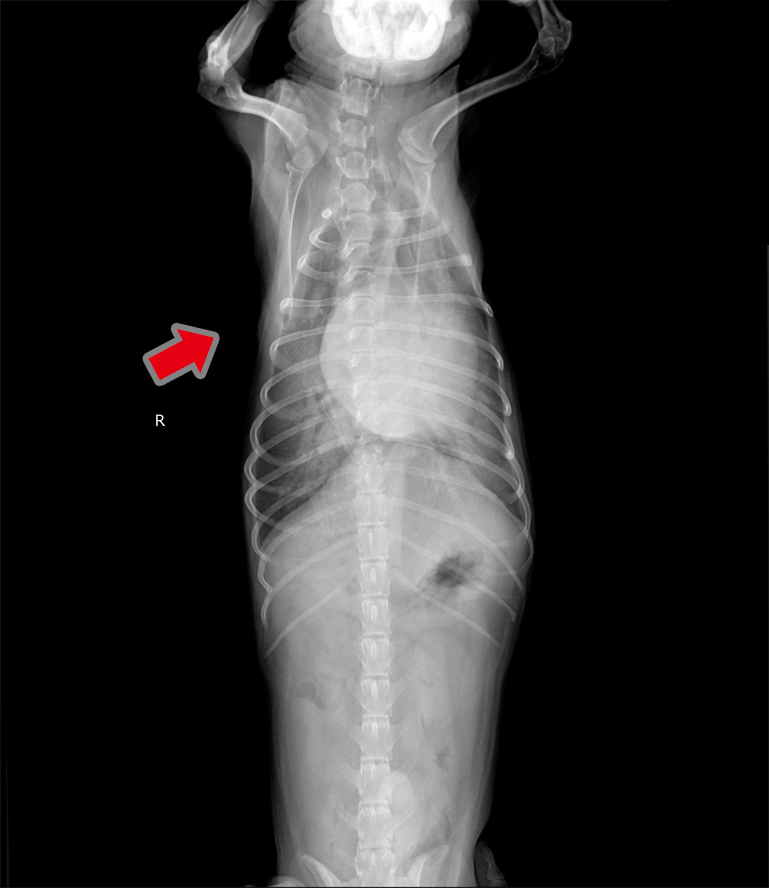

- 肺水腫(治療前)

- 肺水腫(治療後):肺(矢印)が白から黒へ改善